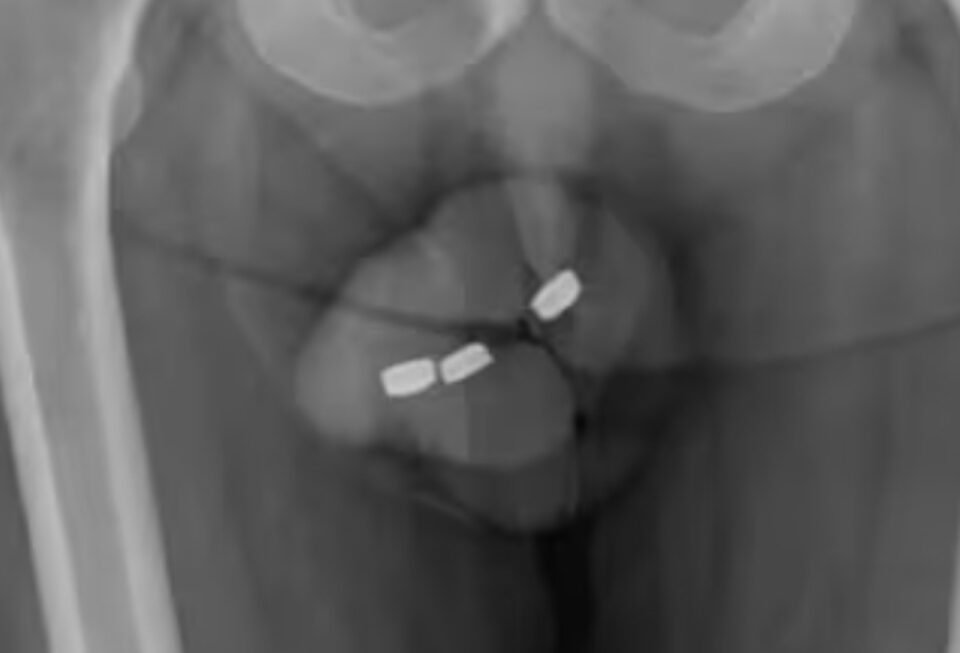

Dilaporkan dari NY Pos, pria itu merasakan nyeri sedang dan diagnosis mengalami parafimosis parah, bahkan terdapat gejala kemih obstruktif. Lantas, dokter segera bertindak melakukan operasi guna mengeluarkan baterai.

Meski demikian, dokter berhasil melepaskan baterai pada kemaluan pria tersebut menggunakan forsep. Akan tetapi, 10 hari kemudian, dia kembali ke rumah sakit akibat pembengkakan. (SP)